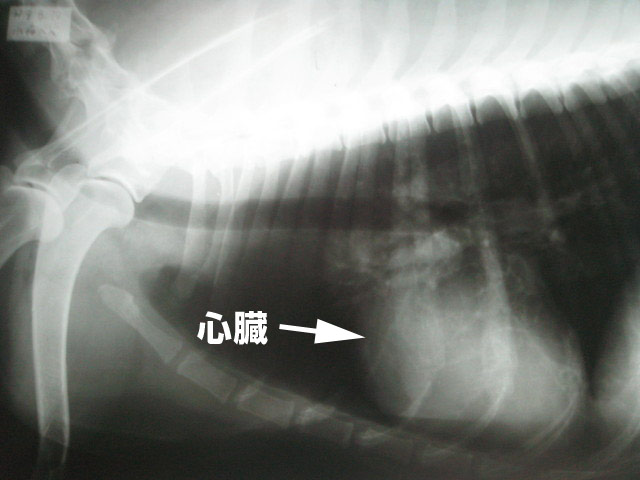

血液検査と、レントゲンも撮った。

前回心電図をとってみて、多少の心肥大はあるけど、肥大と心拍が少しゆっくりなのはトシだからだし、心臓はそんなに心配ないみたい。

上半身。

心臓がちょっと肥大気味。

背骨にはヘルニアっぽいところもあるみたい。